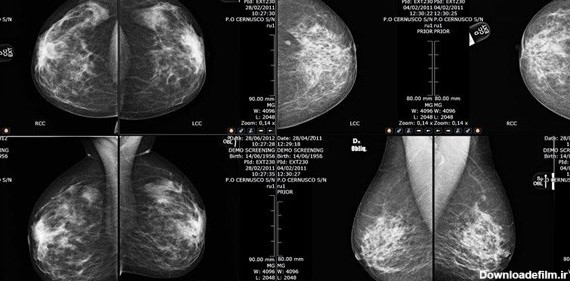

تصاویر ماموگرافی سالم

ماموگرافی نوعی تصویربرداری از سینه است که با دوزهای بسیار کم اشعه ایکس گرفته میشود و در تشخیص توده های خوش خیم و بدخیم پستان بسیار کمک کننده است. ماموگرافی سرطان پستان را ده سال زودتر از زمانی که توده قابل لمس باشد تشخیص می دهد. عوارض ماموگرافی ناشی از رادیواکتیو به مقدار بسیار ناچیز است.

ماموگرافی، تصویربرادی از سینه و از مهمترین ارکان تشخیص سرطان سینه یا هر بیماری سینه است. این سرطان بین خانمها شایع است و باید مرتب سلامت سینه را چک کرد.